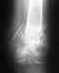

Недавно сильно упал - с велосипеда - точнее вылетел из него, упал на вытянутую руку, в итоге перелом ключицы со смещением . .. 10 дней прходил гипсе, на 11 сделали операцию - вставили спицу и нитью какой- то зафиксировали(лавсановой или кевларовой?), (еще оказалось что были осколки, которых не было видно на ренгене, как бывнутри кости), и снова гипс наложили. Врач сказал что месяц нужно с гипсом ходить, месяц с косынкой, и месяц разрабатывать. . и через полгода вытаскивать спицу. уже отходил 2 недели, рука очень ослабла, ключица уже не болит. Есть ли альтернатива методу который прописал врач? Можно ли сократить сроки, заменить гипс на какую нибудь менее дискомфортную повязку , итп. ? Спасибо